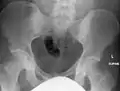

The radiographic appearance of osteopoikilosis on an X-ray is characterized by a pattern of numerous white densities of similar size spread throughout all the bones. This is a systemic condition. It must be differentiated from blastic metastasis, which can also present radiographically as white densities interspersed throughout bone. Blastic metastasis tends to present with larger and more irregular densities in less of a uniform pattern. Another differentiating factor is age, with blastic metastasis mostly affecting older people, and osteopoikilosis being found in people 20 years of age and younger.

The distribution is variable, though it does not tend to affect the ribs, spine, or skull.[2]

Osteopoikilosis of the hips on CT.